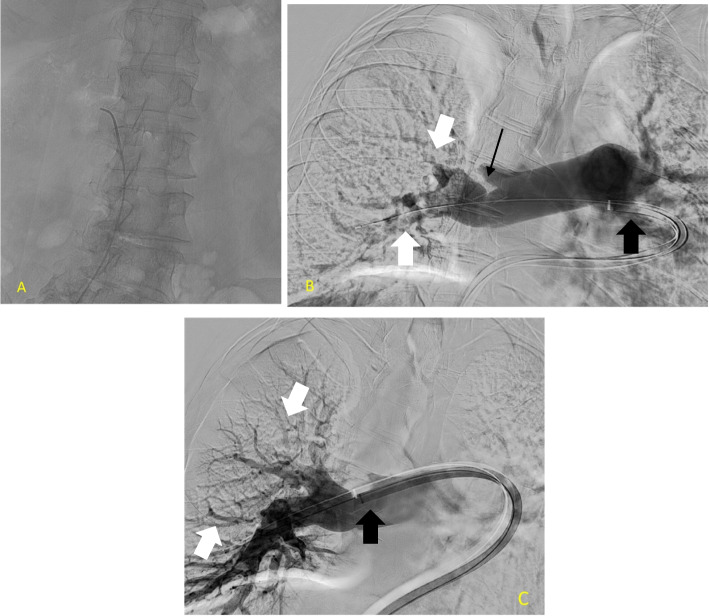

目的:急性肺栓塞(PE)是肺移植受者(LTR)面临的重大挑战,即使有预防性抗凝治疗。由于该人群并发症的风险增加,急性PE的最佳治疗方法仍不确定。本回顾性病例系列旨在阐明使用Inari装置(MT)和导管定向溶栓(CDT)经皮机械取栓治疗肺移植患者急性PE的结果。材料和方法:本研究分析了连续9例经ct血管造影(CTA)证实的肺移植后急性PE患者的治疗结果。治疗干预包括MT或CDT。随访评估包括治疗后至少1年至3年,评估各种参数,包括ICU住院时间、心室压、肺功能和实验室检查。结果:MT和CDT技术成功率均为100%,肺血流恢复顺利,血流动力学参数改善,1年生存率为100%。结论:经皮MT和CDT治疗肺移植患者急性PE是可行和有效的。这些治疗导致血栓快速溶解,治疗后改善,并提高总生存率。

Purpose: Acute pulmonary embolism (PE) presents a significant challenge in lung transplant recipients (LTR), even with prophylactic anticoagulation. Due to the heightened risk of complications in this population, the optimal treatment approach for acute PE remains uncertain. This retrospective case series aims to elucidate the outcomes of percutaneous mechanical thrombectomy with the Inari device (MT) and catheter-directed thrombolysis (CDT) in managing acute PE in lung transplant patients.

Materials and methods: This study examines the treatment outcomes of nine consecutive post-lung transplantation patients with acute PE confirmed with Computed Tomography Angiography (CTA). Treatment interventions included either MT or CDT. Follow-up assessments encompassed a minimum of one year and up to 3 years post-treatment, evaluating various parameters including ICU stay, ventricular pressures, pulmonary function, and laboratory tests.

Results: Both MT and CDT achieved a 100% technical success rate, leading to the successful restoration of pulmonary blood flow and improvements in hemodynamic parameters, with a one-year survival rate of 100%.

Conclusion: Percutaneous treatments, including MT and CDT, demonstrate feasibility and efficacy in managing acute PE among lung transplant patients. These treatments lead to rapid thrombus resolution, post-treatment improvements, and enhanced overall survival.